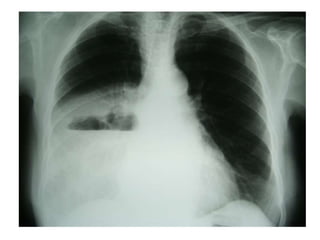

• #51 Paciente masculino de 63 años que refiere tos, disnea y dolor torácico derecho de aproximadamente siete días de evolución. El examen físico revela hipo ventilación en hemitorax derecho. Como dato positivo de laboratorio presenta VSG aumentada. Se solicita inicialmente una radiografía de tórax frente en la cual se observa, radioopacidad basal derecha con broncograma aéreo que borra el seno costofrénico homolateral. Engrosamiento pleural difuso que impresiona comprometer pleura mediastínica. Dados los hallazgos en la radiografía se decide ampliar el diagnostico solicitándole una TAC de tórax con contraste endovenoso en la cual se observa engrosamiento circunferencial pleural de hemitorax derecho. Atelectasia de segmentos inferiores con broncograma aéreo. Pequeña área líquida tabicada. Adenomegalias mediastinales en región prevascular, pretraqueal retrocavo y ventana aortopulmonar. Caja torácica sin alteraciones tomográficamente demostrables. Estructura y densitometría osteoarticular de l raquis dorsal normal. DIAGNOSTICOS DIFERENCIALES: • Engrosamiento pleural: Derrame organizado, hemotórax, piotorax, cirugía previa, radioterapia, exposición al Asbesto. • Tumores Benignos: lipomas, tumores fibrosos, esplenosis torácica. • Tumores malignos: MTTS de pulmón, mama, linfoma. • Mesotelioma maligno. DIAGNOSTICO DEFINITIVO: • MESOTELIOMA MALIGO